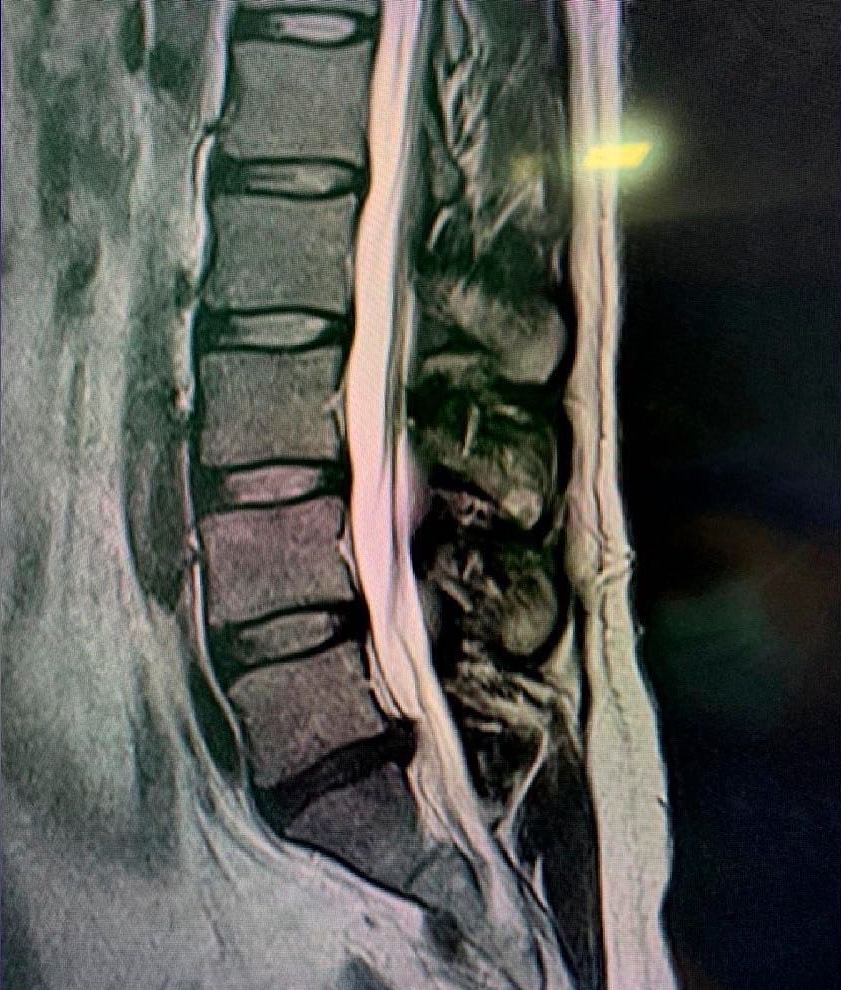

Las enfermedades del disco es probablemente la enfmerdad que con mayor frecuencia tratan los neurocirujanos y cirujanos de columna. Prolapso de disco agudo, disco abultado, hernia de disco o disco roto son términos comúnmente utilizados para describir las fallas de esta estructura. Cuando los síntomas son nuevos, la secuencia típica es dolor de espalda en la región del disco seguido de dolor de irritación nerviosa en el brazo o la pierna. Esto se llama dolor radicular, y algunas personas usan el término ciática cuando la pierna está afectada.

Un prolapso de disco de larga data puede presentarse con dolor crónico de espalda, cuello, brazo, hombro o pierna, en cualquier combinación. Las tres partes de la columna vertebral móvil pueden verse afectadas, pero es mucho más probable que las regiones lumbar y cervical causen síntomas. Esto se debe a la movilidad relativa y las cargas colocadas en estas regiones.

Los síntomas causan dolor que suele empeorar con la carga y se alivia con el reposo o las posiciones flexionadas. El dolor de brazos o piernas es muy común y, cuando es más intenso, puede haber entumecimiento o debilidad de una extremidad o disfunción de la mano. La distribución del dolor o síntomas neurológicos está determinada por el nervio afectado y depende de si el disco es de origen cervical, torácico o lumbar. Cuando hay compresión de la médula espinal, la marcha, el equilibrio y la continencia pueden verse afectados. La cirugía está indicada si existe un problema neurológico importante o si el dolor no responde bien a medidas simples. La discectomía simple, la microdiscectomía, la discectomía mínimamente invasiva o la discectomía cervical anterior y la artrodesis pueden ser muy eficaces en pacientes seleccionados que no responden al reposo, la analgesia y otras medidas conservadoras.

Otra problema que comúnmente afecta al disco es la enfermedad discal degenerativa que puede provocar síntomas incapacitantes como dolor, pérdida de las fuerza en extremidades, dificultad para la marcha etc . Esto puede afectar a cualquier región o zona de la columna vertebral, pero principalmente a la columna cervical y lumbar. Estos problemas pueden llegar a requerir tratamientos que van van desde la fisioterapia hasta cirugías complejas que involucran el reemplazo de discos y soporte con tornillos.